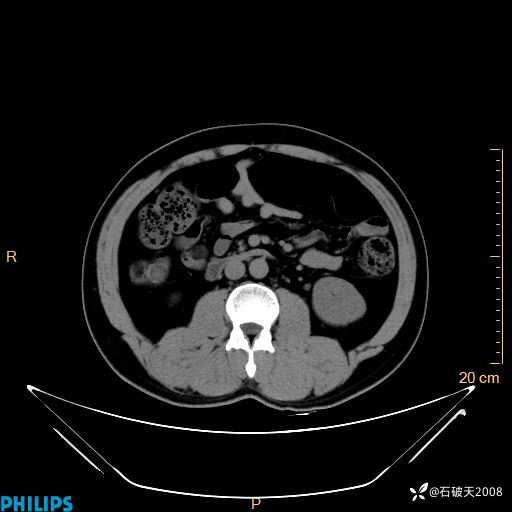

冠状位

MIP